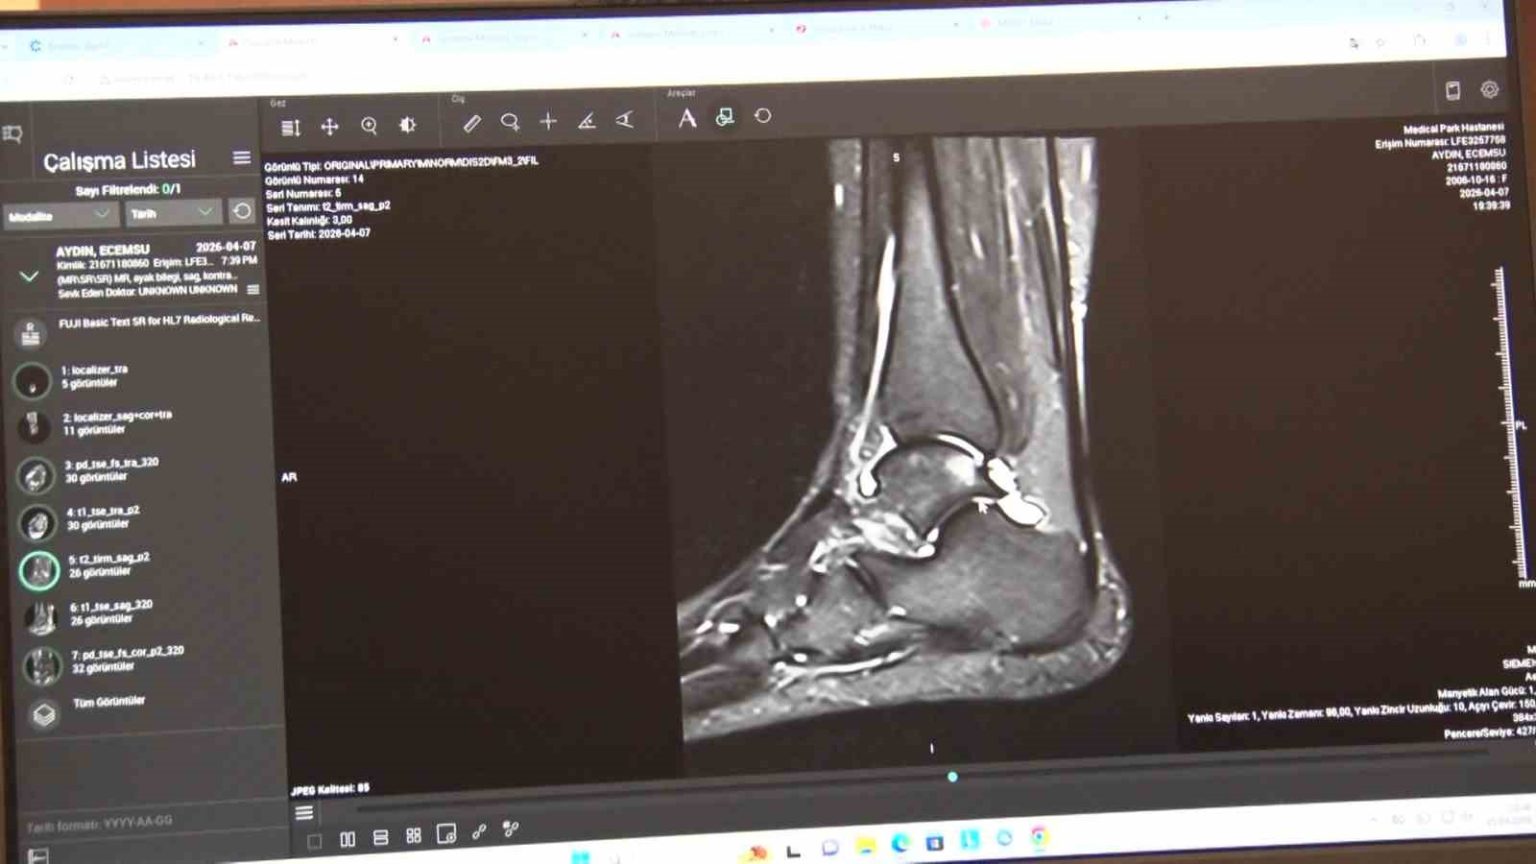

En sık görülen yaralanmalar diz ve tendonlarda

Klinik pratikte en sık karşılaştıkları spor yaralanmalarına da değinen Serarslan, özellikle halı sahada yapılan futbolun sakatlık riskini artırdığını belirterek, “Bizim klinik pratiğimizde en sık karşılaştığımız sakatlıkları birkaç gruba ayırabiliriz. Birincisi ani travmayla gelişen akut yaralanmalar, ikincisi ise zamanla tekrarlayan zorlanmalara bağlı oluşan kronik problemler. En çok karşılaştığımız akut travmalar arasında diz yaralanmaları, ön çapraz bağ yaralanmaları, menisküs yaralanmaları, kas travmaları, kas yırtıkları, omuz çıkıkları, omuz bağ ve kas yırtıkları ile özellikle aşil tendon yaralanmaları yer alıyor. Türkiye’de halı sahada futbol çok yaygın ama bu zemin sakatlık açısından da çok riskli bir alan oluşturuyor” ifadelerini kullandı.